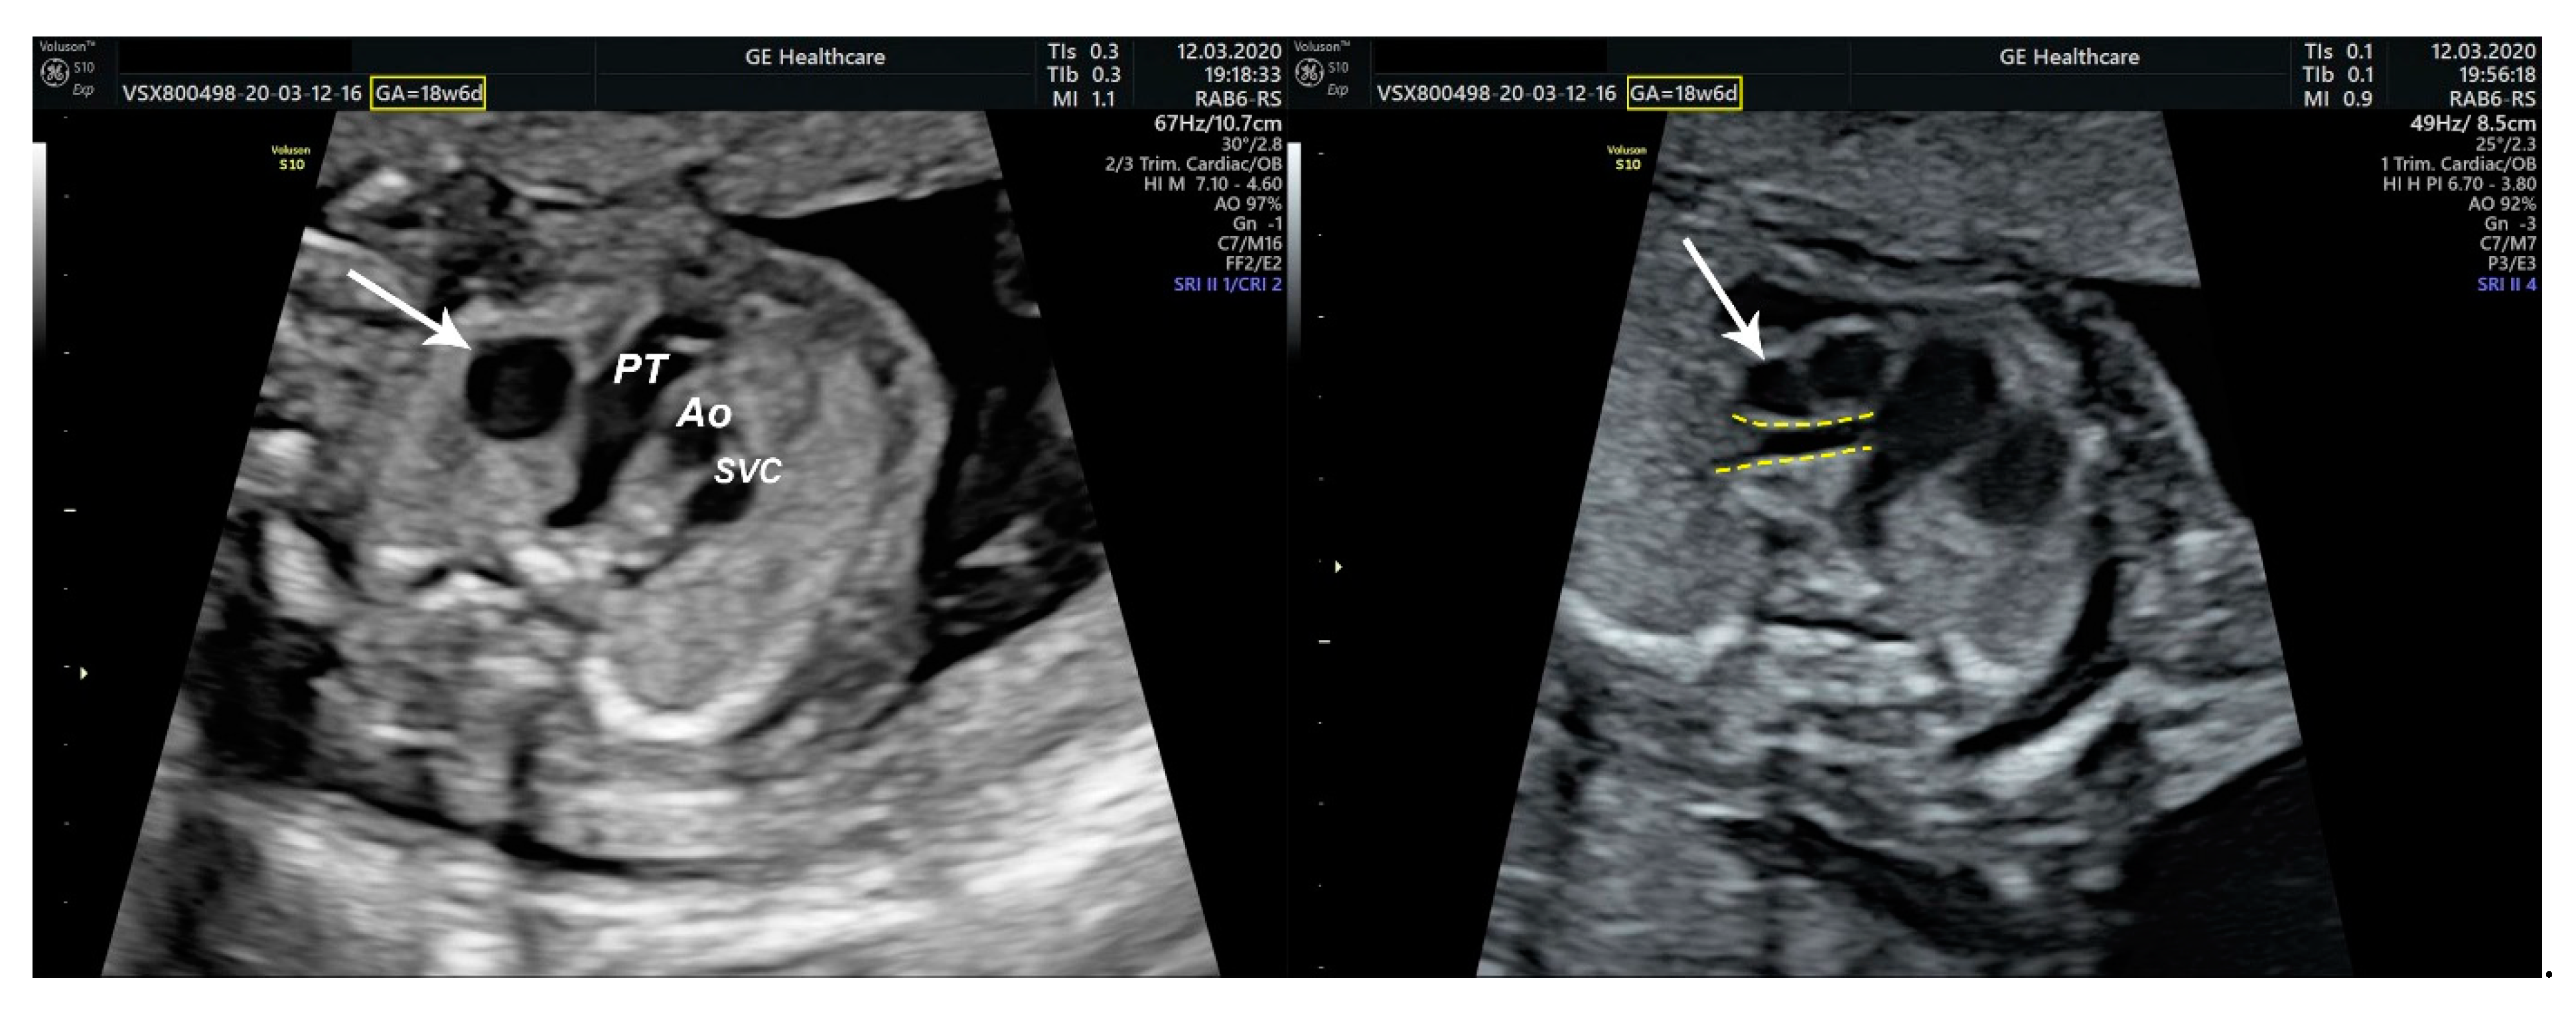

2.1. Ultrasound Findings

- an isolated aortic arch anomaly (supposedly aneurysmal dilation from which the left common carotid artery emerges) and coarctation of the aorta with the anterograde flow;

- ventricular septal defect, coarctation of the aorta, and a vascular formation located superior from the aortic arch with the appearance of an arteriovenous fistula;

- aneurysmal dilation located above the pulmonary trunk bifurcation and a dilated left common carotid artery with a retrograde flow;